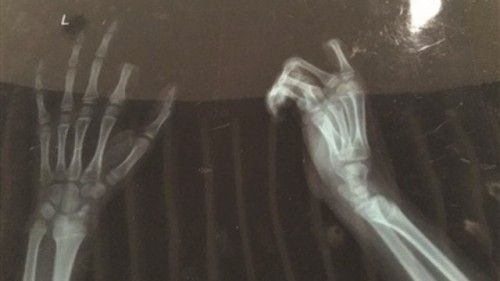

Awalnya, ibu dari anak tersebut menegurnya karena ia selalu bermain ponsel semenjak ia bangun tidur, sehingga membuat contoh buruk bagi adiknya yang berusia 6 tahun. Tidak mengindahkan teguran ibunya, sang anak malah berbalik bicara kepada ibunya. Tidak suka, ibunya pun melaporkannya kepada sang ayah yang kemudian memarahinya tersebut. Karenanya, sang anak pun mengambil pisau yang ada di dekatnya kemudian memotong jari telunjuk kirinya sendiri. Orang tuanya yang syok pun segera melarikannya ke rumah sakit untuk bisa menyambungkan kembali jarinya melalui operasi, walau hasilnya membutuhkan setidaknya seminggu hingga jarinya bisa tersambung sempurna kembali.